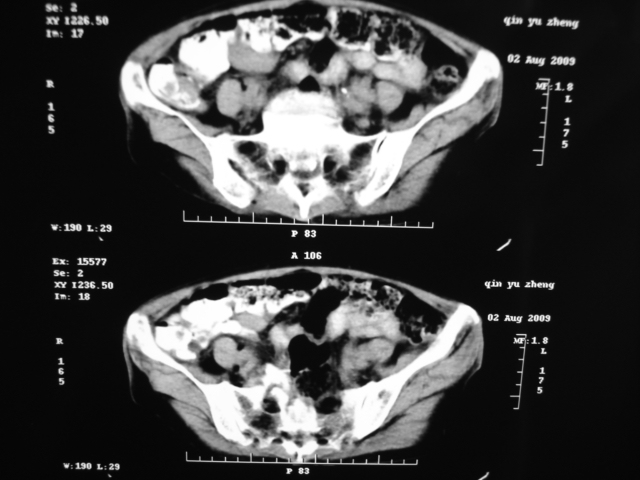

同事奶奶,73岁,腹痛一年,夜晚较重,潜血+++,拒绝增强,考虑左肾ca并腹膜后转移;请各位老师帮忙看看,谢谢!

左肾癌侵及输尿管上段,腹膜后多发淋巴结转移,脾脏钙化灶。至于潜血+++,要考虑消化道病变,本次ct片肠腔未见明显异常。

1)考虑左肾癌侵犯肾盂并腹膜后淋巴结转移。2)脾脏钙化灶。

考虑左肾癌侵犯肾盂并腹膜后淋巴结转移。